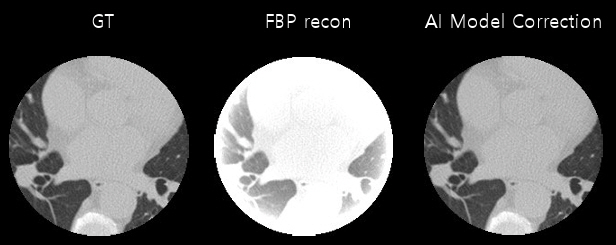

ROI 이미징은 CBCT 기반 영상에서 방사선 노출을 최소화하면서 진단 및 시술에 꼭 필요한 영역만 고해상도로 확인하고자 하는 접근 방식이다[11]. 이 방식은 전체 FOV를 모두 스캔하지 않고, 목표 부위만 집중적으로 투사‧재구성함으로써 주변 조직의 불필요한 방사선 노출을 줄이는 장점을 지닌다. 이를 구현하기 위해서는 Interior Tomography 개념을 적용하여 ROI 밖 투사 데이터를 생략하거나 저해상도로 취급하게 되는데, 이때 FOV에서 제외된 영역으로 인해 트렁케이션(Truncation) 아티팩트가 발생하기 쉽다. 그림 3과 같이 밝은 테두리(Bright-Rim) 현상 등 영상 왜곡이 생길 수 있으며, 그대로 FBP(Filtered Back Projection) 알고리즘을 적용할 경우 영상 품질이 크게 저하된다[12].

그림 3

C-arm ROI CT 이미지

출처 Reprinted with permission from K.H. Son et al., “CNN-based region-of-interest image reconstruction from truncated data in cone-beam CT,” in Proc. SPIE Med. Imag., (San Diego, CA, USA), vol. 12031, Mar. 2022, pp. 518-523.

이러한 문제를 해결하고자, 필터 최적화 및 TV (Total Variation) 기반 IR 기법이 제안되었으며, 최근에는 딥러닝을 접목한 복원 방식이 적극 연구되고 있다. 예를 들어, 트렁케이션으로 결손된 투사 정보를 보정하기 위해 U-Net, GAN 등 신경망 모델이 활용되는데, 영상 재구성 후 남는 아티팩트를 제거하거나 투영 단계에서 누락된 데이터를 학습된 방식으로 보완하는 전략이 대표적이다. 또한, CS와 IR 알고리즘을 결합해 잡음을 줄이면서 ROI 내부는 고해상도로 유지할 수 있게 되면서, 더욱 적은 투영 각도‧데이터량으로도 임상적으로 유의미한 영상 품질을 확보하게 되었다.